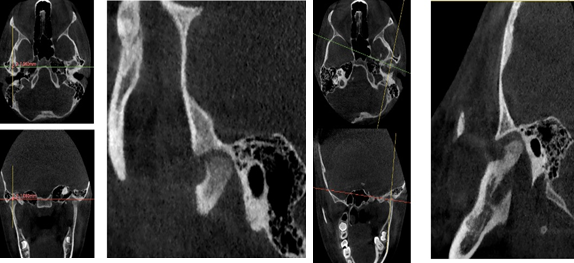

A través de los cortes tomográficos (Figura 3) se pudo observar que la rama mandibular derecha medía 43.85 mm y la izquierda 39.53 mm dando una diferencia de 4.34 mm lo que evidencia que la asimetría que presenta la paciente es a causa de la discrepancia de tamaño de las ramas mandibulares (A).

En el corte a nivel de la articulación temporomandibular izquierda se observó un aplanamiento del cóndilo con áreas de cambios osteoartríticos leves (B); en la articulación temporomandibular derecha el cóndilo se encuentra con una severa osteoartritis que muestra una imagen hipodensa a nivel condilar compatible con un quiste subcondral (C).

Diagnóstico de ATM: La paciente presenta una displasia discal sin reducción bilateral.

Plan de tratamiento: Debido a todo lo expuesto se decidió colocar un aparato de avance mandibular tipo monoblock para recapturar el disco. Para ello se inició con la realización de una mordida constructiva para la confección del aparato, se llevó a una coincidencia de las líneas media y un adelantamiento mandibular de 3 mm (Figuras D, E y F). Posteriormente se envió los registros para la confección del dispositivo de avance mandibular tipo monoblock (Klammt Clase II) que fue instalado en marzo del 2023 constatando de que se encuentre totalmente adaptado (G), las indicaciones de uso fueron más de 20 horas al día aconsejando que la paciente se lo retire únicamente para comer y para el aseo respectivo. Los controles se realizaron a las 2 semanas y después con una frecuencia mensual durante 12 meses.